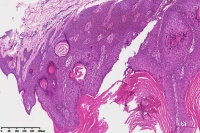

脂溢性角化症伴皮角?

性别

女

年龄

49岁

手臂皮肤组织

图2

脂溢性角化病